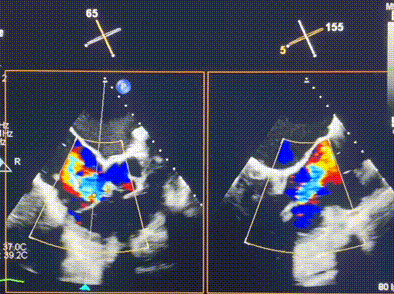

術(shù)前超聲提示重度三尖瓣反流

術(shù)中輸送器在超聲引導下調(diào)整位置